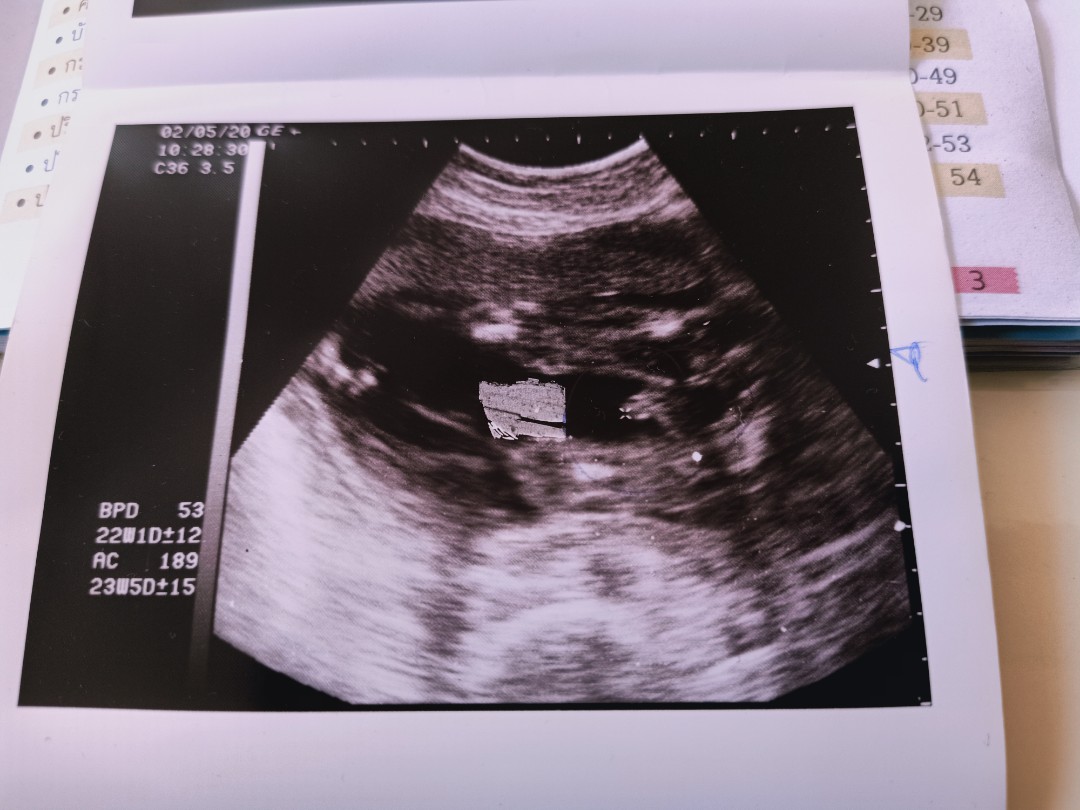

5เดือนแล้ว ผมดิ้นเก่งมากเลยแม่

หมอบอกว่าได้ลูกชายจ้าาา ❤️❤️❤️ ทีมกันยาจ้า✌️✌️

ดิ้นเก่งเหมือนกันเลยค่ะกะว่าซาวด์ดูเพศมาดิ้นหนีไม่ยอมให้ดูสักทีกว่าจะเห็นได้หลายนาทีเลยค่ะไม่ยอมนิ่ง ผู้ชายค่ะ22วีค คลอด6กันยา